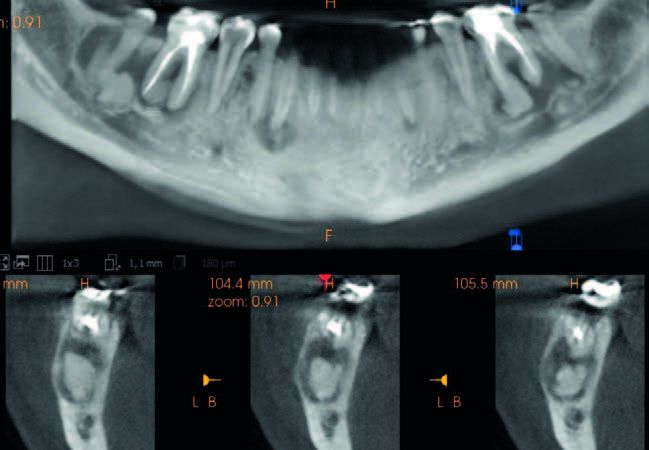

En 2023 se llevó a cabo una nueva evaluación radiográfica, complementada con un CBCT (Figura 3). En el estudio se identificaron áreas hiperdensas bien definidas, correspondientes a las regiones de los dientes 36, 43, 46 y 47. Estas áreas estaban rodeadas por un halo radiotransparente de forma irregular, sugiriendo la presencia de material mineralizado dentro de un tejido fibroso menos denso. Esas características radiográficas eran compatibles con un patrón intermedio de DCOF, que incluye la transición típica desde una fase predominantemente radiotransparente a una fase mixta.

En noviembre de 2024, la paciente acudió a consulta presentando una fractura vertical en el molar 36, lo que requirió su exodoncia. A nivel radiográfico (Figura 4), se observó un aumento significativo de material radiodenso en la zona, particularmente en la región de la raíz mesial.

En el presente caso clínico, en 2018 se observaron lesiones proliferativas e inmaduras con una apariencia radiotransparente. En etapas más avanzadas de maduración, se identificaron masas radiodensas en las radiografías panorámica realizadas en 2021 y 2023. Estas masas hiperdensas, localizadas en las regiones de los dientes 36, 46, 47 y 43, estaban rodeadas por un área hipodensa y adheridas a las raíces de los dientes correspondientes. Las lesiones estaban bien delineadas del hueso circundante. Muchos autores han informado la presencia de un borde radiotransparente circundante característico y distintivo en la DCO13.